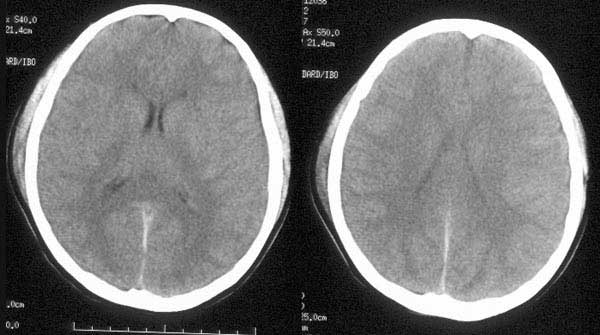

患者入院后予脱水治疗,并于10小时后行ct复查:

ct诊断:1、左颞硬膜下血肿已吸收消失。

2、蛛网膜下腔出血量较前增多。

3、脑肿胀程度较前明显改善。